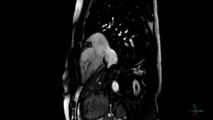

IRM cardiaque filme les battement d'un cœur en temps réel